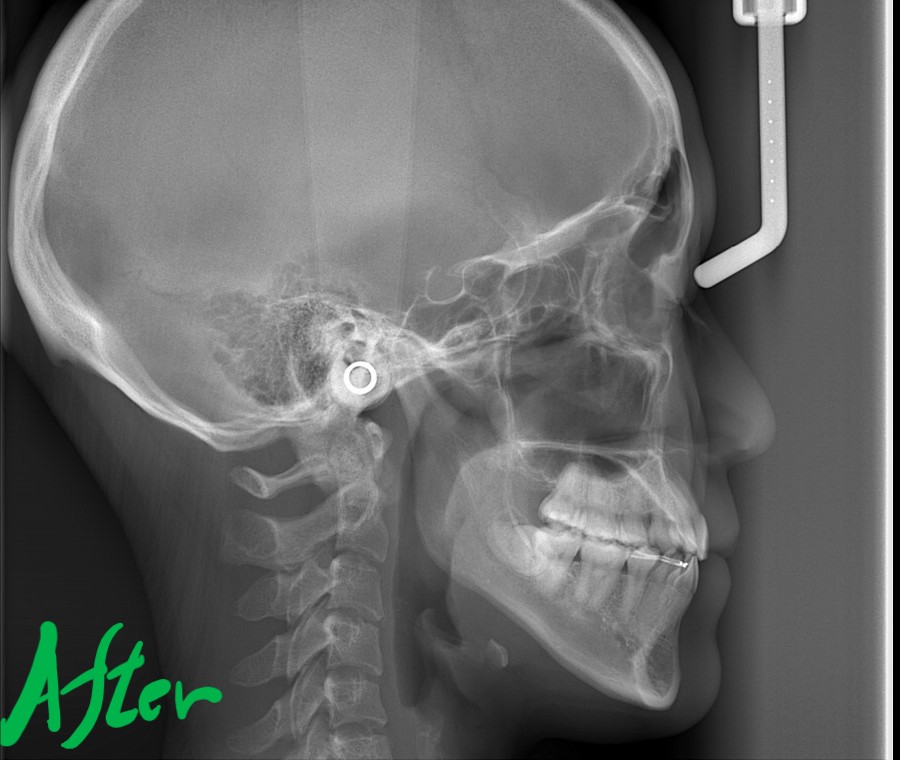

レントゲン写真でも矯正治療前後を比較してみましょう